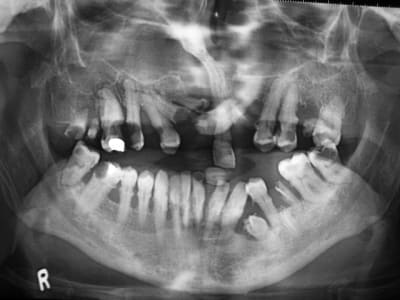

Patient vu la semaine dernière: bec-de-lièvre, prognathe, bègue...

Et la radio ne rend pas compte de la position des dents...

La 23 recouvre la 11 (!)dans le sens transversale.

ce qui m'épate c'est que même le "R" de la radiographie (indiquant Right) est de biais...il a vraiment pas de bol...j'espère que la pano ne lui est pas tombée dessus.

OUi, enfin prendre la photo de la pano en la pliant pour faire des vagues c'est pas malin non plus.